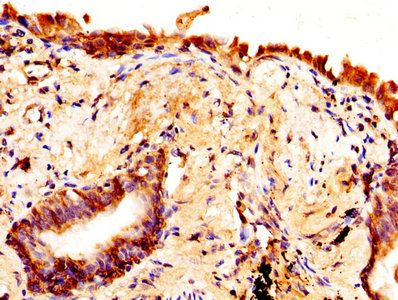

IHC image of CSB-PA11137A0Rb diluted at 1:370 and staining in paraffin-embedded human lung cancer performed on a Leica BondTM system. After dewaxing and hydration, antigen retrieval was mediated by high pressure in a citrate buffer (pH 6.0). Section was blocked with 10% normal goat serum 30min at RT. Then primary antibody (1% BSA) was incubated at 4°C overnight. The primary is detected by a biotinylated secondary antibody and visualized using an HRP conjugated SP system.